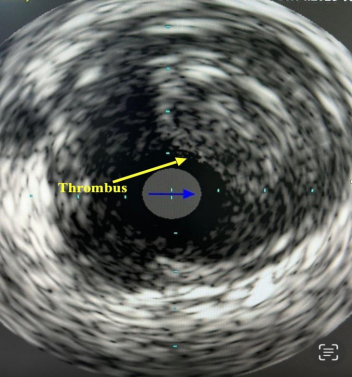

The patient was started on intravenous Tirofiban and, after approximately 36 hours, was brought back to the cardiac catheterization laboratory. An improvement in the haziness of the mid-segment left anterior descending artery (LAD) picture was noted, with TIMI-3 flow remaining (Figure 3). Intravascular ultrasound (IVUS) confirmed the presence of an ectatic segment with a large amount of mobile thrombus (Figure 4).

Figure 4. Baseline IVUS image showing a large thrombus (yellow arrow).